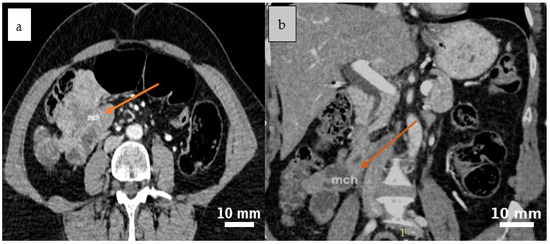

2.4. Diagnostic Assessment

3.2. Clinical and Imaging Features

3.2.3. Role and Limitations of Imaging